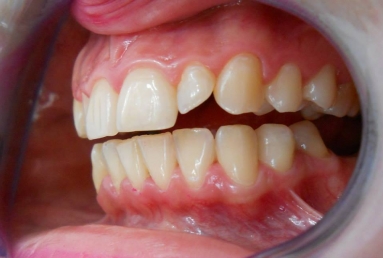

Very small lateral incisors covered with full ceramic crowns and ceramic veneers on central incisors. The prosthetic space was correctly split between the four incisors, in order to reduce the disproportion between the large centrals and the very small laterals. The preparation of the teeth was minimally invasive, all four incisors remained vital.